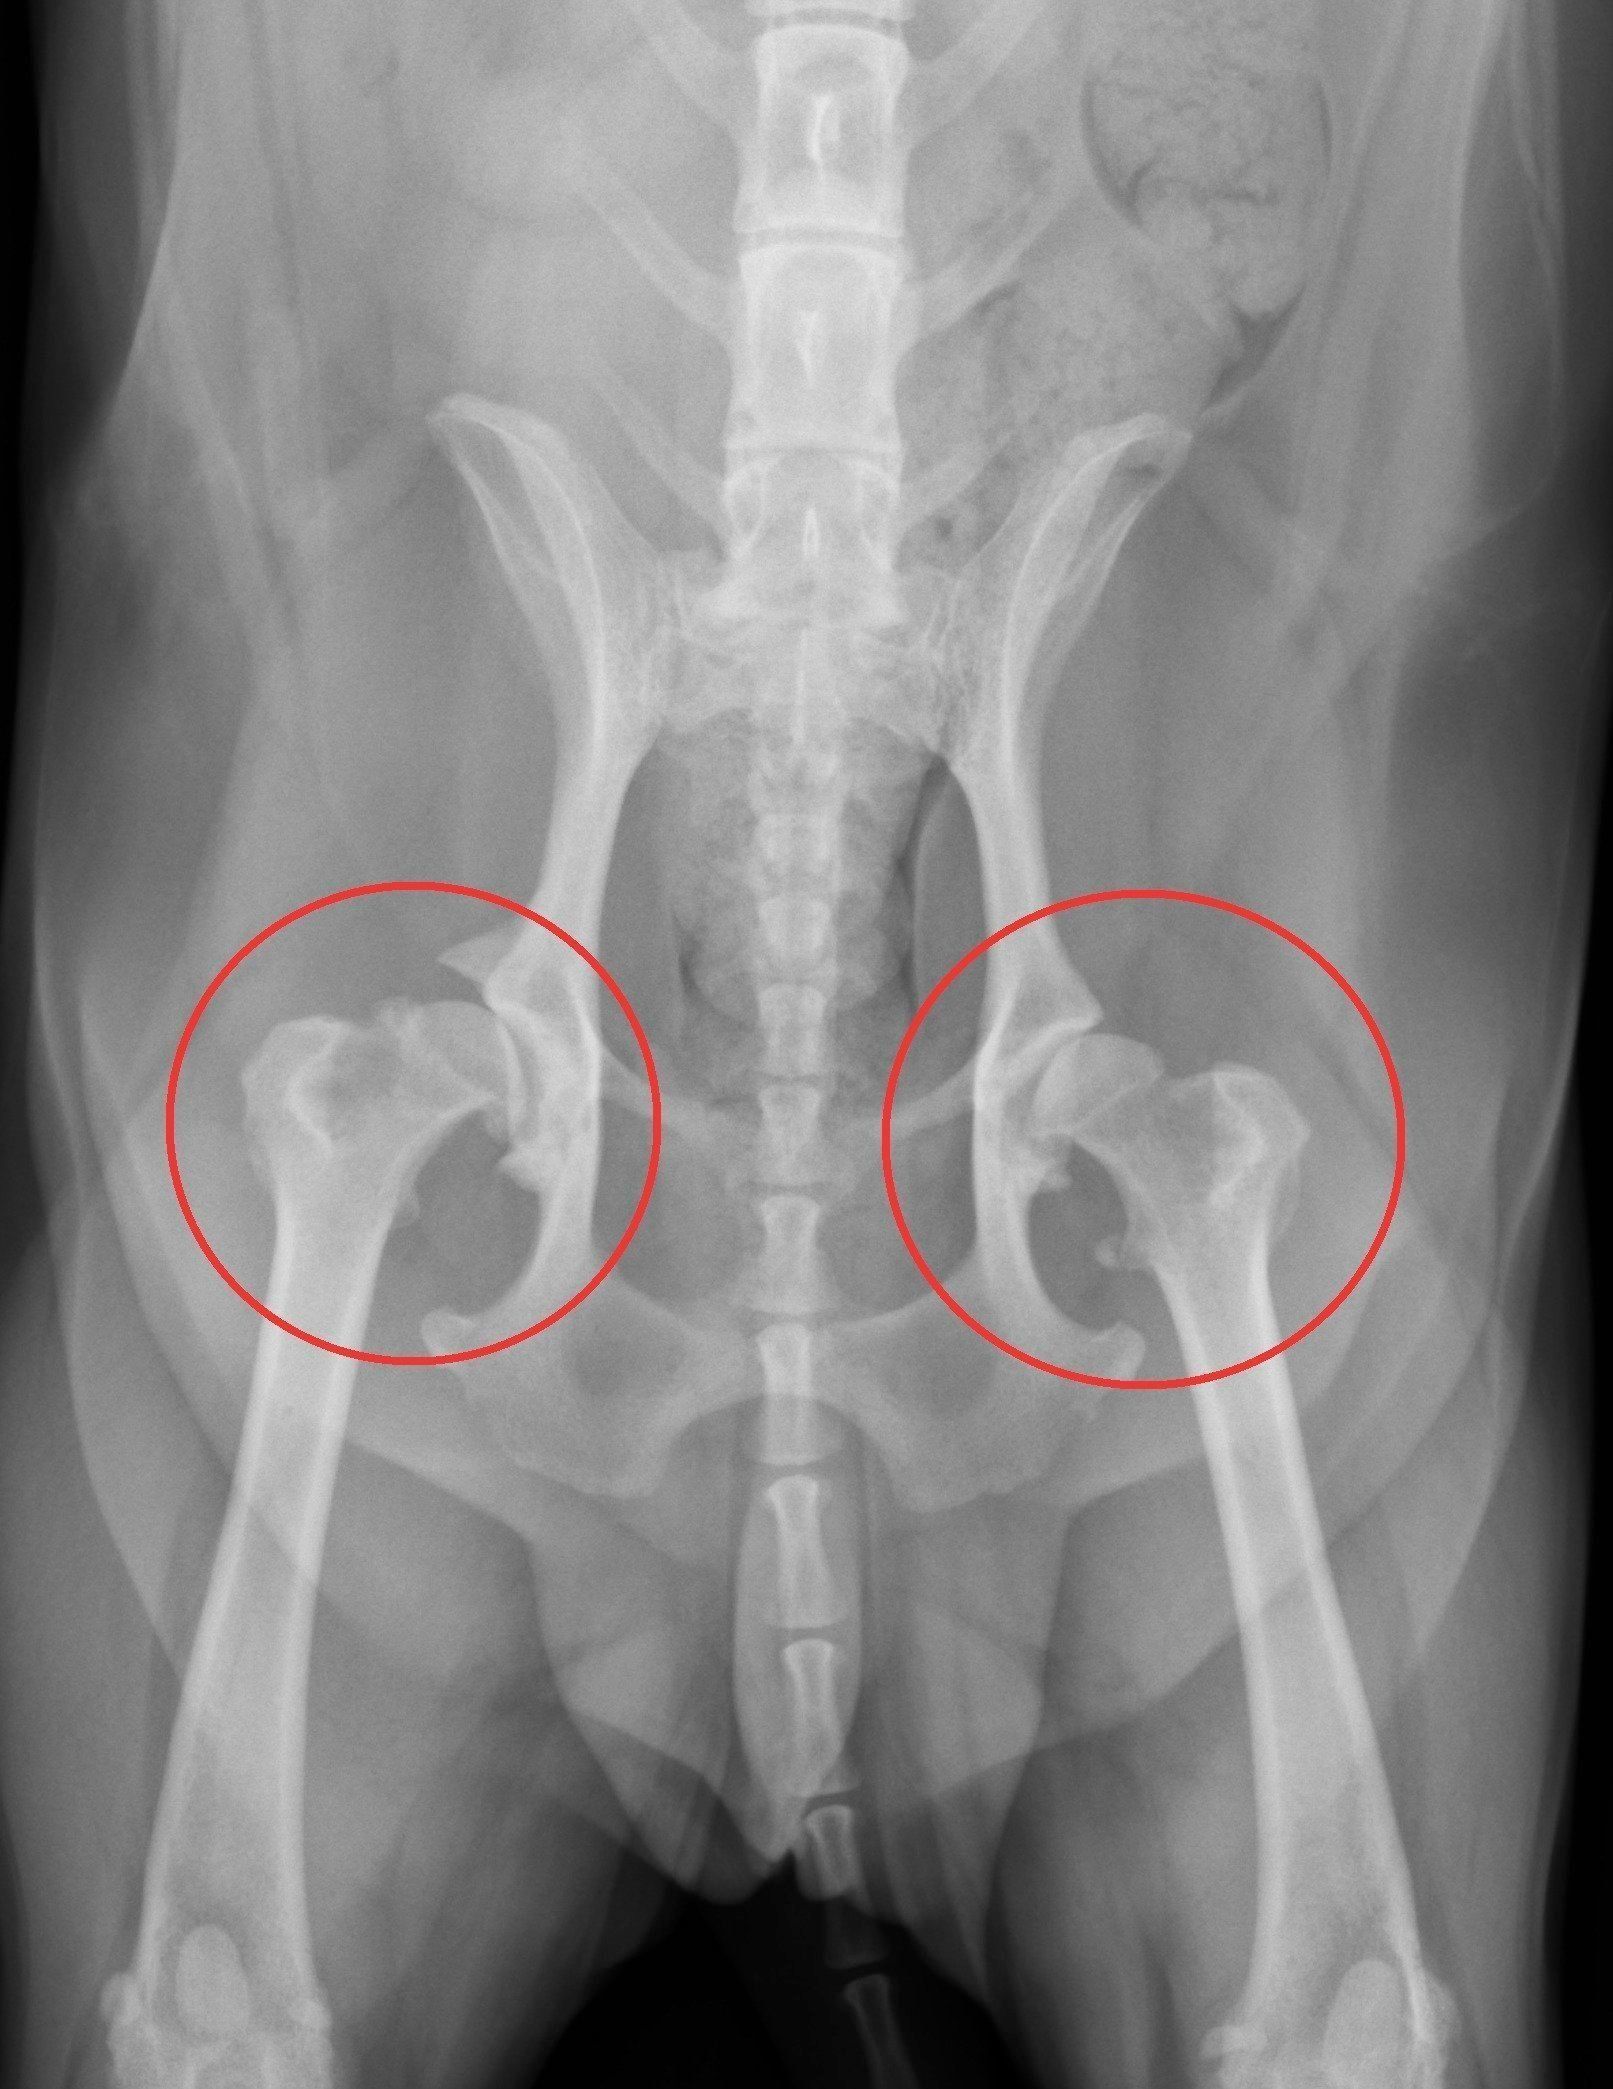

症例写真提供/ノヤ動物病院

画像は、両足に股関節形成不全が見られる、2才のフレンチ・ブルドッグのエックス線写真。赤い丸で囲まれた部分で形成不全を発症しています。